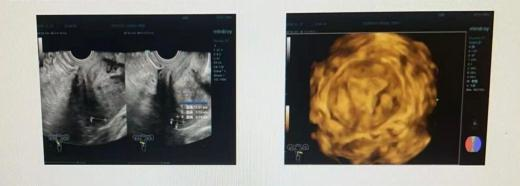

现病史:既往月经规则,周期30天,经期7天,经量多,有剧烈痛经,末次月经2024-6-30(长期服用地诺孕素至2周前停药),量与性质同前。患者3年前出现经量增多,最多1小时湿透1片夜用卫生巾,伴血块,贫血(具体不详),经期同前,伴痛经,VAS7分,以左下腹明显,需口服止痛药,无同房疼痛,无腹泻,无恶心呕吐,未就诊。2024-05来院检查,超声提示“子宫腺肌症合并子宫多发小肌瘤、内膜回声不均、双卵巢内囊性块、右卵巢旁囊性块”,盆腔提示“子宫腺肌病(Ⅱ型),合并子宫多发肌瘤。双卵巢内异囊肿。盆腔子宫内膜异位(深部浸润型)”,门诊予口服地诺孕素治疗;后月经未来、无腹痛、异常阴道流血不适。2周前因乳腺结节增大予停用地诺孕素,现无腹痛腹胀不适,要求手术来院。

术后诊断:子宫平位,大小5.3*5.1*5.4 cm,内膜厚0.45 cm(双层),后壁肌层增厚,回声不均,宫区另见多个低回声,较大位于前壁1.3*1.2*0.7 cm,边界清。左卵巢内见1.5*1.5*0.9 cm囊性回声,内呈絮状偏强回声,血流不明显。右卵巢正常大,回声无殊。右卵巢旁见2.3*2.0*1.5 cm囊性回声,内液清。

影像所见:子宫后倾,稍增大变形,轮廓清楚光整,子宫后壁外肌层稍增厚、厚约2.6 cm,信号不均;肌层见3-4枚小等T1短T2占位灶,界清,较大位于前壁约1.1 *0.9 *1.2 cm;内膜信号未见异常。子宫右宫底后壁浆膜面见斑点状短T1信号,局部与直肠前壁粘连,可见斑片状影,范围1.8 *1.2 *0.9 cm。右侧卵巢显示大小、形态及信号未见明显异常。左侧卵巢见1.5 *1.0 *1.3 cm短T1不均长T2信号。盆腔淋巴结未见明显肿大。盆底少量积液。